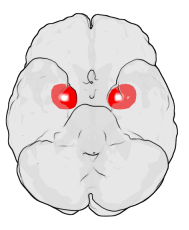

최신 뇌과학 연구와 향후 전망

최근 뇌영상 연구는 편도체가 단순한 감정 처리기를 넘어, 사회적 뇌(social brain)의 중심이라는 점을 강조합니다. Xiong et al.(2022)은 Molecular Psychiatry에서 사회적 고립이 편도체의 구조적 변화와 전전두엽과의 연결 약화를 초래할 수 있음을 보여주었습니다. 이는 코로나19 팬데믹 기간의 사회적 격리 경험이 뇌 구조에 직접적인 영향을 미칠 수 있다는 점을 시사합니다. 또한 Nagasawa et al.(2015)은 인간과 반려견이 서로 응시할 때 쌍방의 옥시토신이 증가하며, 이때 편도체와 연관된 사회적 보상 회로가 활성화된다고 보고했습니다. 향후 연구들은 편도체의 역할을 정신질환 치료, 사회성 증진 훈련, 반려동물-인간 관계 강화 프로그램 등에 응용할 수 있을 것입니다.